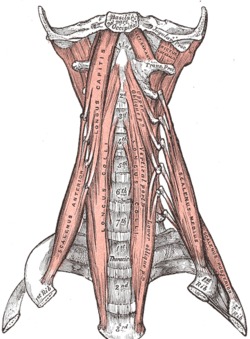

In the lateral part of the occipital bone, extending lateralward from the posterior half of the condyle is a quadrilateral or triangular plate of bone, the jugular process, excavated in front by the jugular notch, which, in the articulated skull, forms the posterior part of the jugular foramen.

It serves as the insertion of the rectus capitus lateralis.